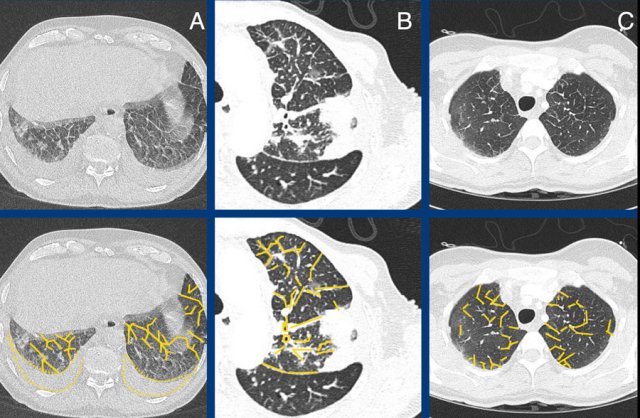

The images show examples of non-fibrotic reticulation due to interstitial thickening in pulmonary edema (A), lymphangitic carcinomatosis (B), and eosinophilic infiltration in eosinophilic granulomatis with polyangitis [EGPA, former Churg-Strauss syndrome] (C).